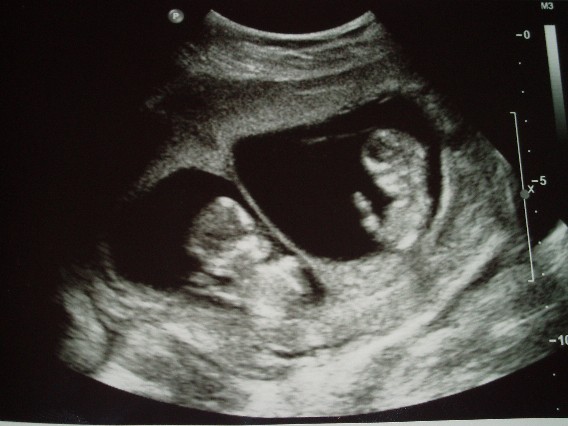

A Baba:

Kép

B Baba:

Együtt:

Kép[/quote]

Fantasztikusak a képek. Tök jó, hogy együtt is le vannak fotózva. Látszik már az orrcsontjuk is, ami nagyon jó jel. Jajj, nagyon édesek. :D :D